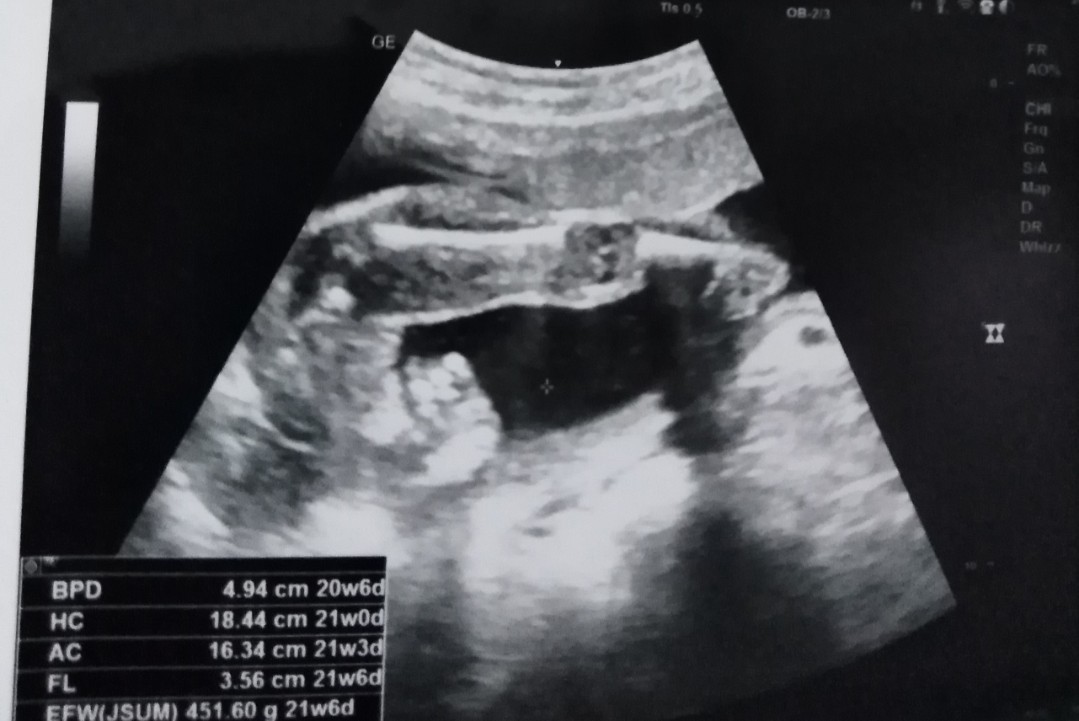

ขอดูใบซาวด์แม่เพศ ชาย หญิง หน่อยค่ะ

ลูกสาว จ้า

เพศหญิงค่ะ

สาวน้อยค่ะ

ลูกสาวค่ะ